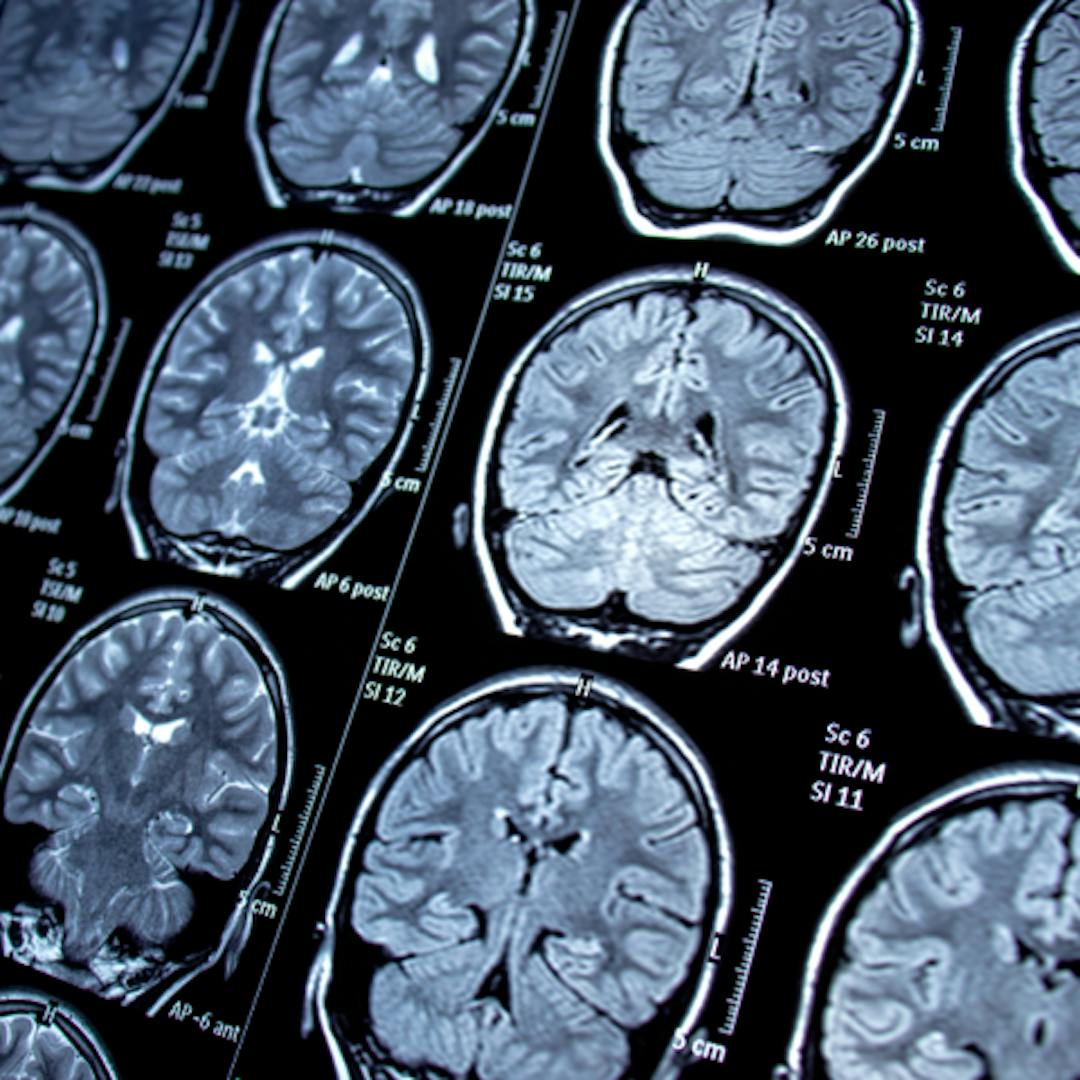

Figure 1: Representative brain activity and clinical presentation of seizures.

Beniczky S, Trinka E, Wirrell E, et al. Updated classification of epileptic seizures: Position paper of the International League Against Epilepsy. Epilepsia. 2025. PMID: 40264351. and Sadiq MT, Akbari H, Rehman AU, et al. Exploiting Feature Selection and Neural Network Techniques for Identification of Focal and Nonfocal EEG Signals in TQWT Domain. J Healthc Eng. 2021. PMID: 34659691.